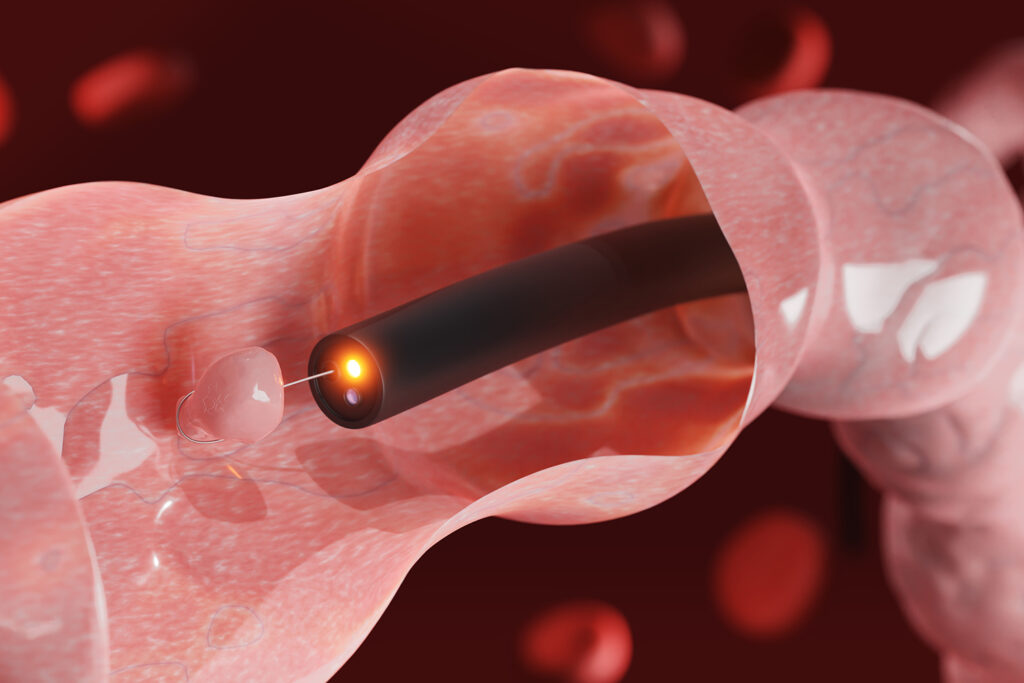

Phương pháp nội soi

Thông thường, khối u vòm họng sẽ thấy được khi nội soi ở giai đoạn đầu của bệnh. Bác sĩ sẽ dùng những dụng cụ chuyên dụng để phát hiện bất thường trong vòm họng và đánh giá mức độ nghiêm trọng của khối u.